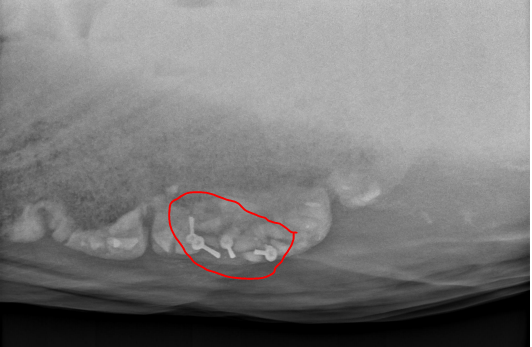

Cependant, il n’est pas sorti d’affaire… Cette petite canaille a 4 CLOUS dans ses intestins…

Du jamais vu selon les vétérinaires…clous qui peuvent le blesser à tout moment 😥